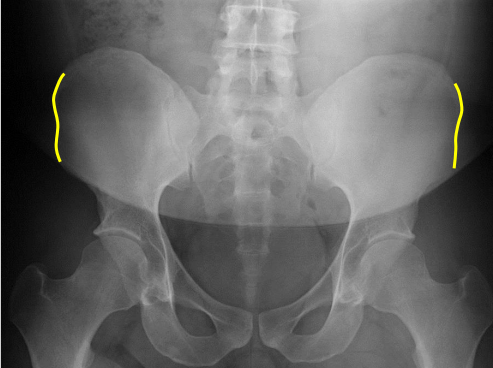

Lateral iliac crests

Femur heads